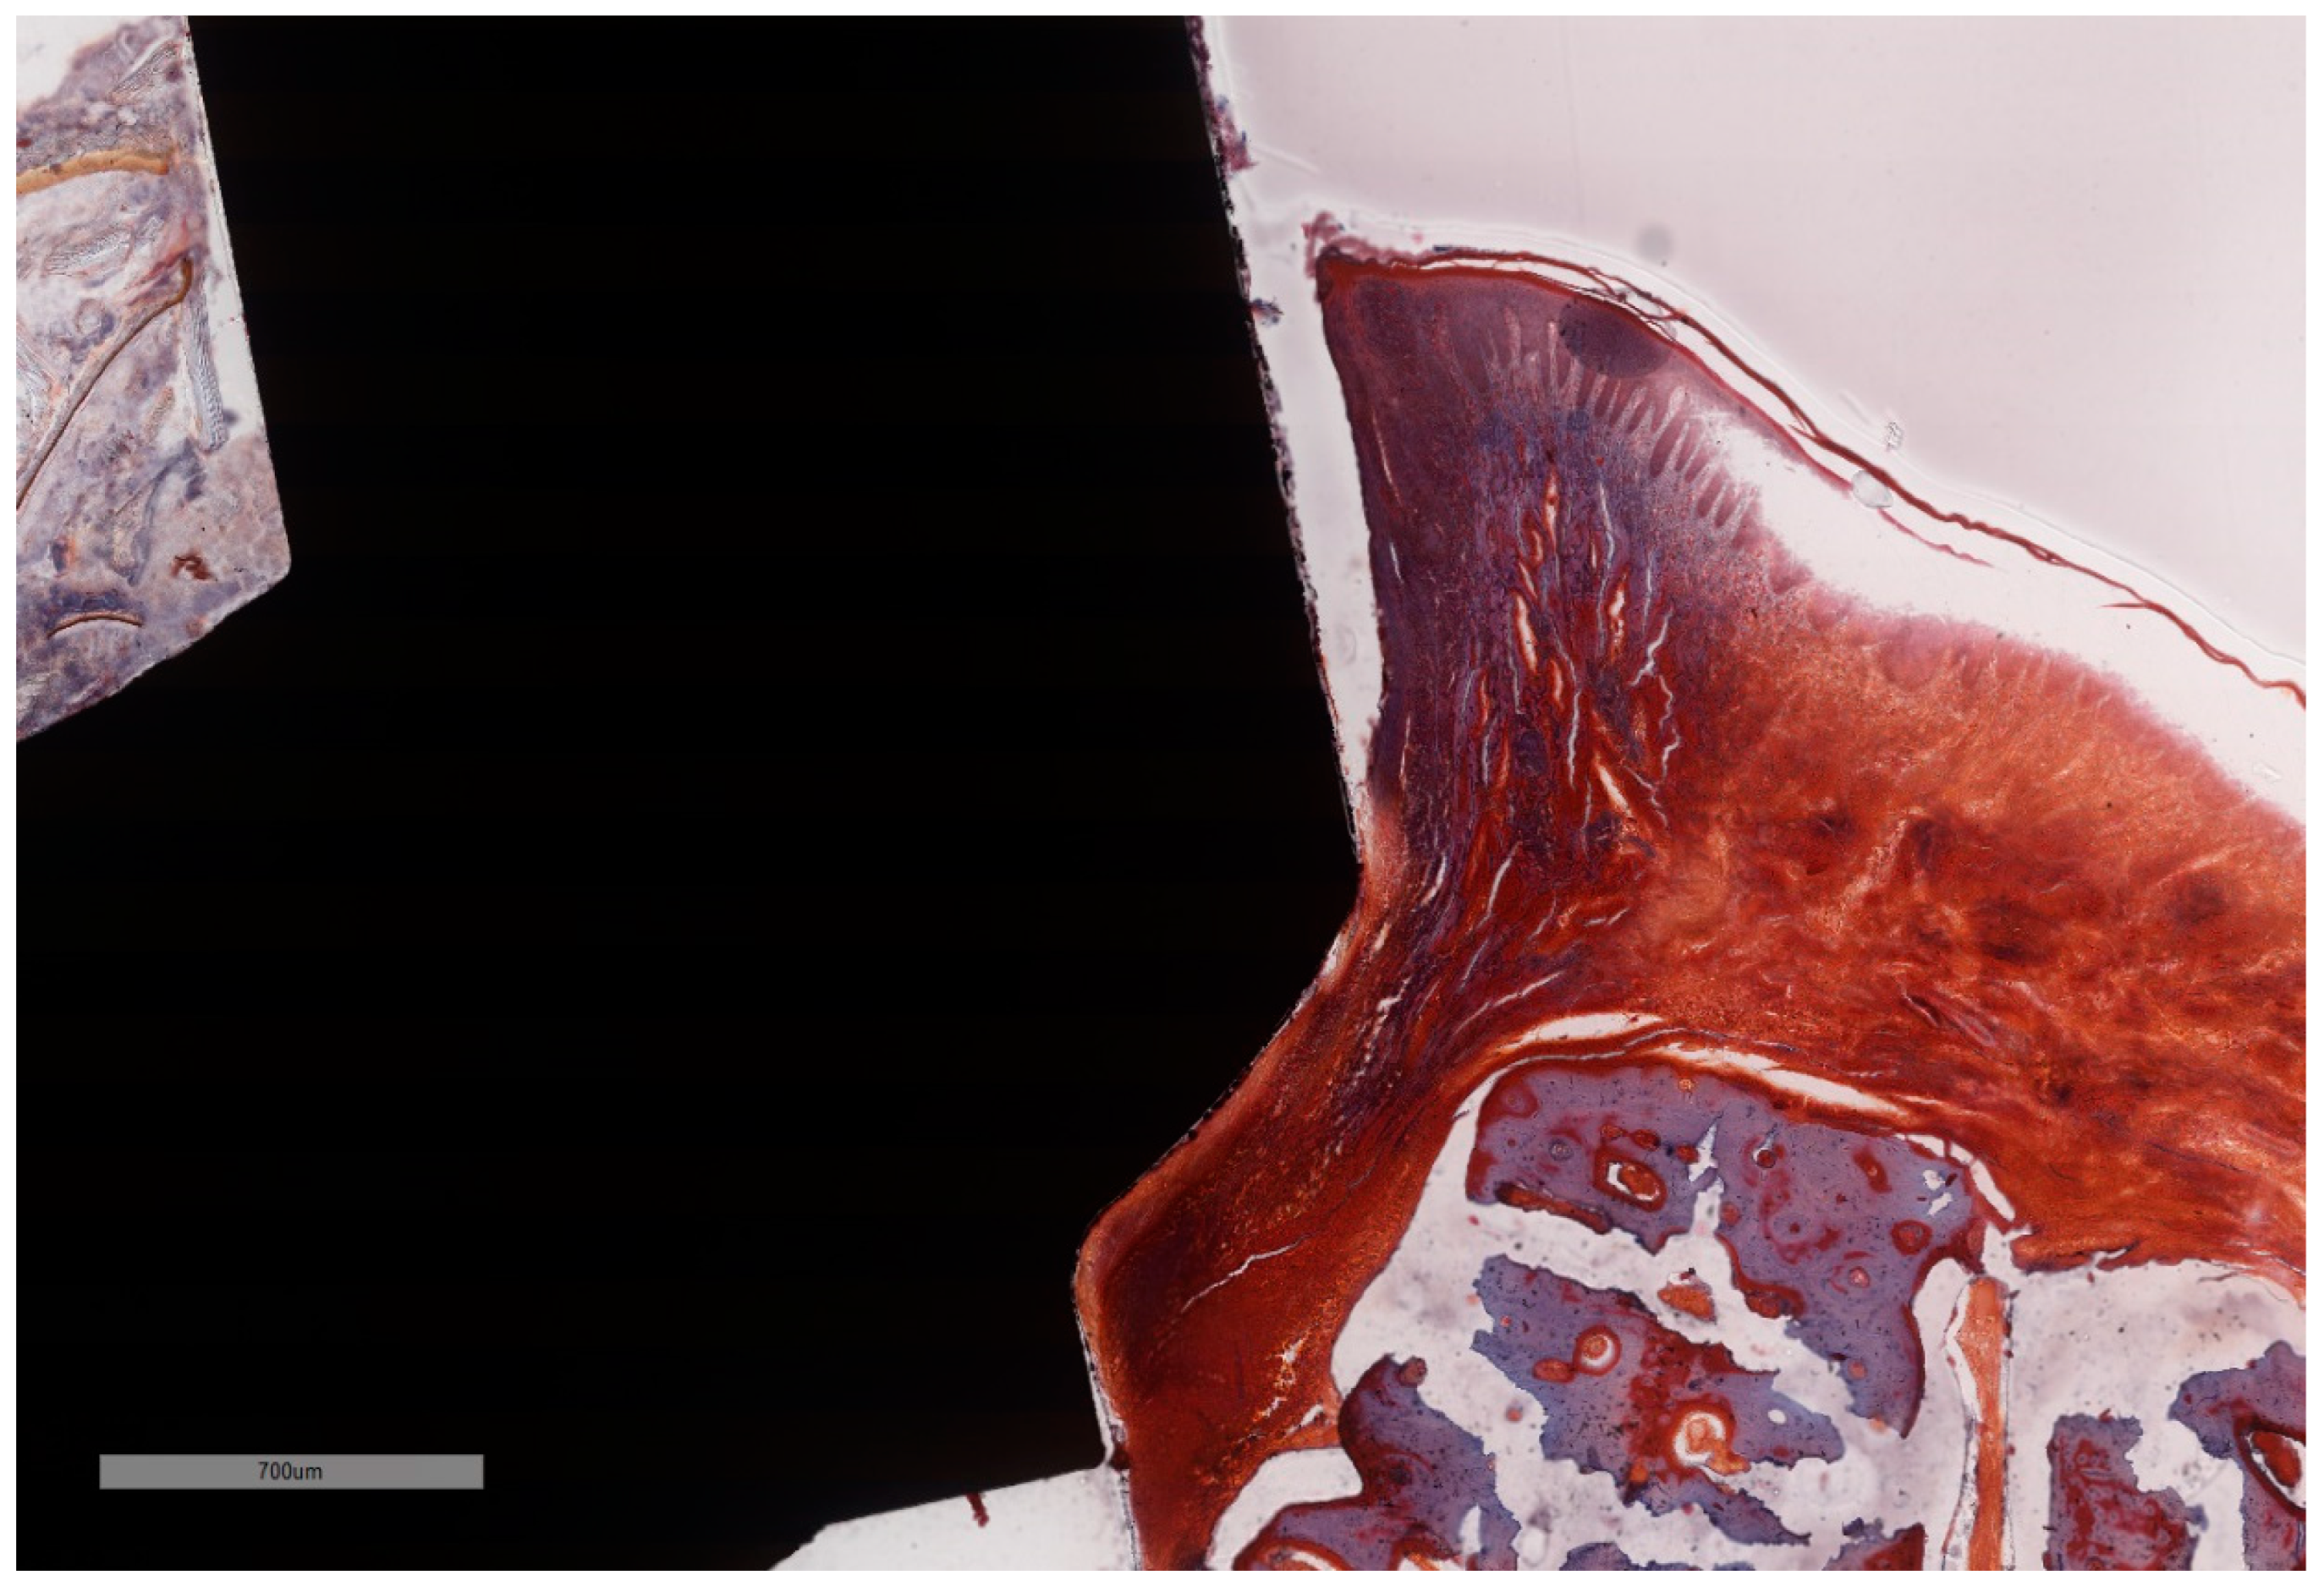

Figure 7. Histomorphometric landmarks identified on both buccal and lingual aspects in each implant: 1—implant shoulder (IS); 2—implant surface at the level of the bone crest (imp); 3—bone crest, defined as the most coronal point of the bone (BC); 4—bottom of the bone defect (BD); 5—margin of the peri-implant mucosa (PM); 6—the apical termination of the junctional epithelium (aJE); 7—the coronal level of the infiltrated connective tissue (cICT); 8—the apical extension of the infiltrated connective tissue (aICT); 9—the most apical extension of the submarginal biofilm that was interposed between the implant and the pocket epithelium of the peri-implant mucosa (aPlaque). (Implant #5, mirroring sections, (A)—Masson Goldner Anilin blue stain, (B)—Movat Pentachrome stain, original magnification ×2).